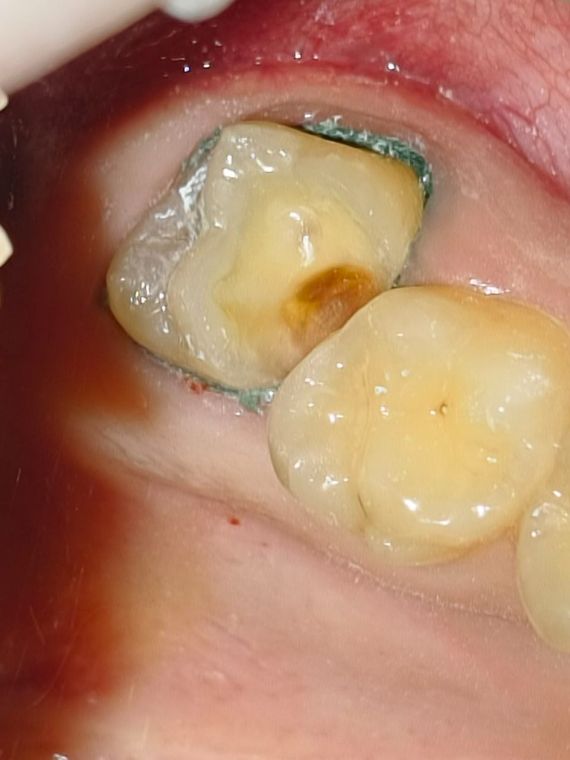

как выглядит зубной кариес на жевательном зубе

На фото представлен глубокий кариес на жевательном зубе

зуб до лечения

Глубокий кариес на жевательной поверхности легко определяется врачом при осмотре, зуб изменен в цвете с светло желтого на сероватый, можно обнаружить полости темного цвета в которых застревает стоматологический зонд.

Во время лечения

При вскрытие эмали зуба, визуализируется кариозные ткани КИД (кариес инфицированный дентин)

окрашивание

Так же видно что ткани размягчины, и легко убираются ручными инструментами. Полость очень обьемная и глубокая

Мягкий дентин

В данном случае темная ткань это - CAD дентин - это часть зуба, которая повреждена кариесом. Такие ткани допустимо сохранить, для того чтобы не депульпировать зуб и оставить его "живым"